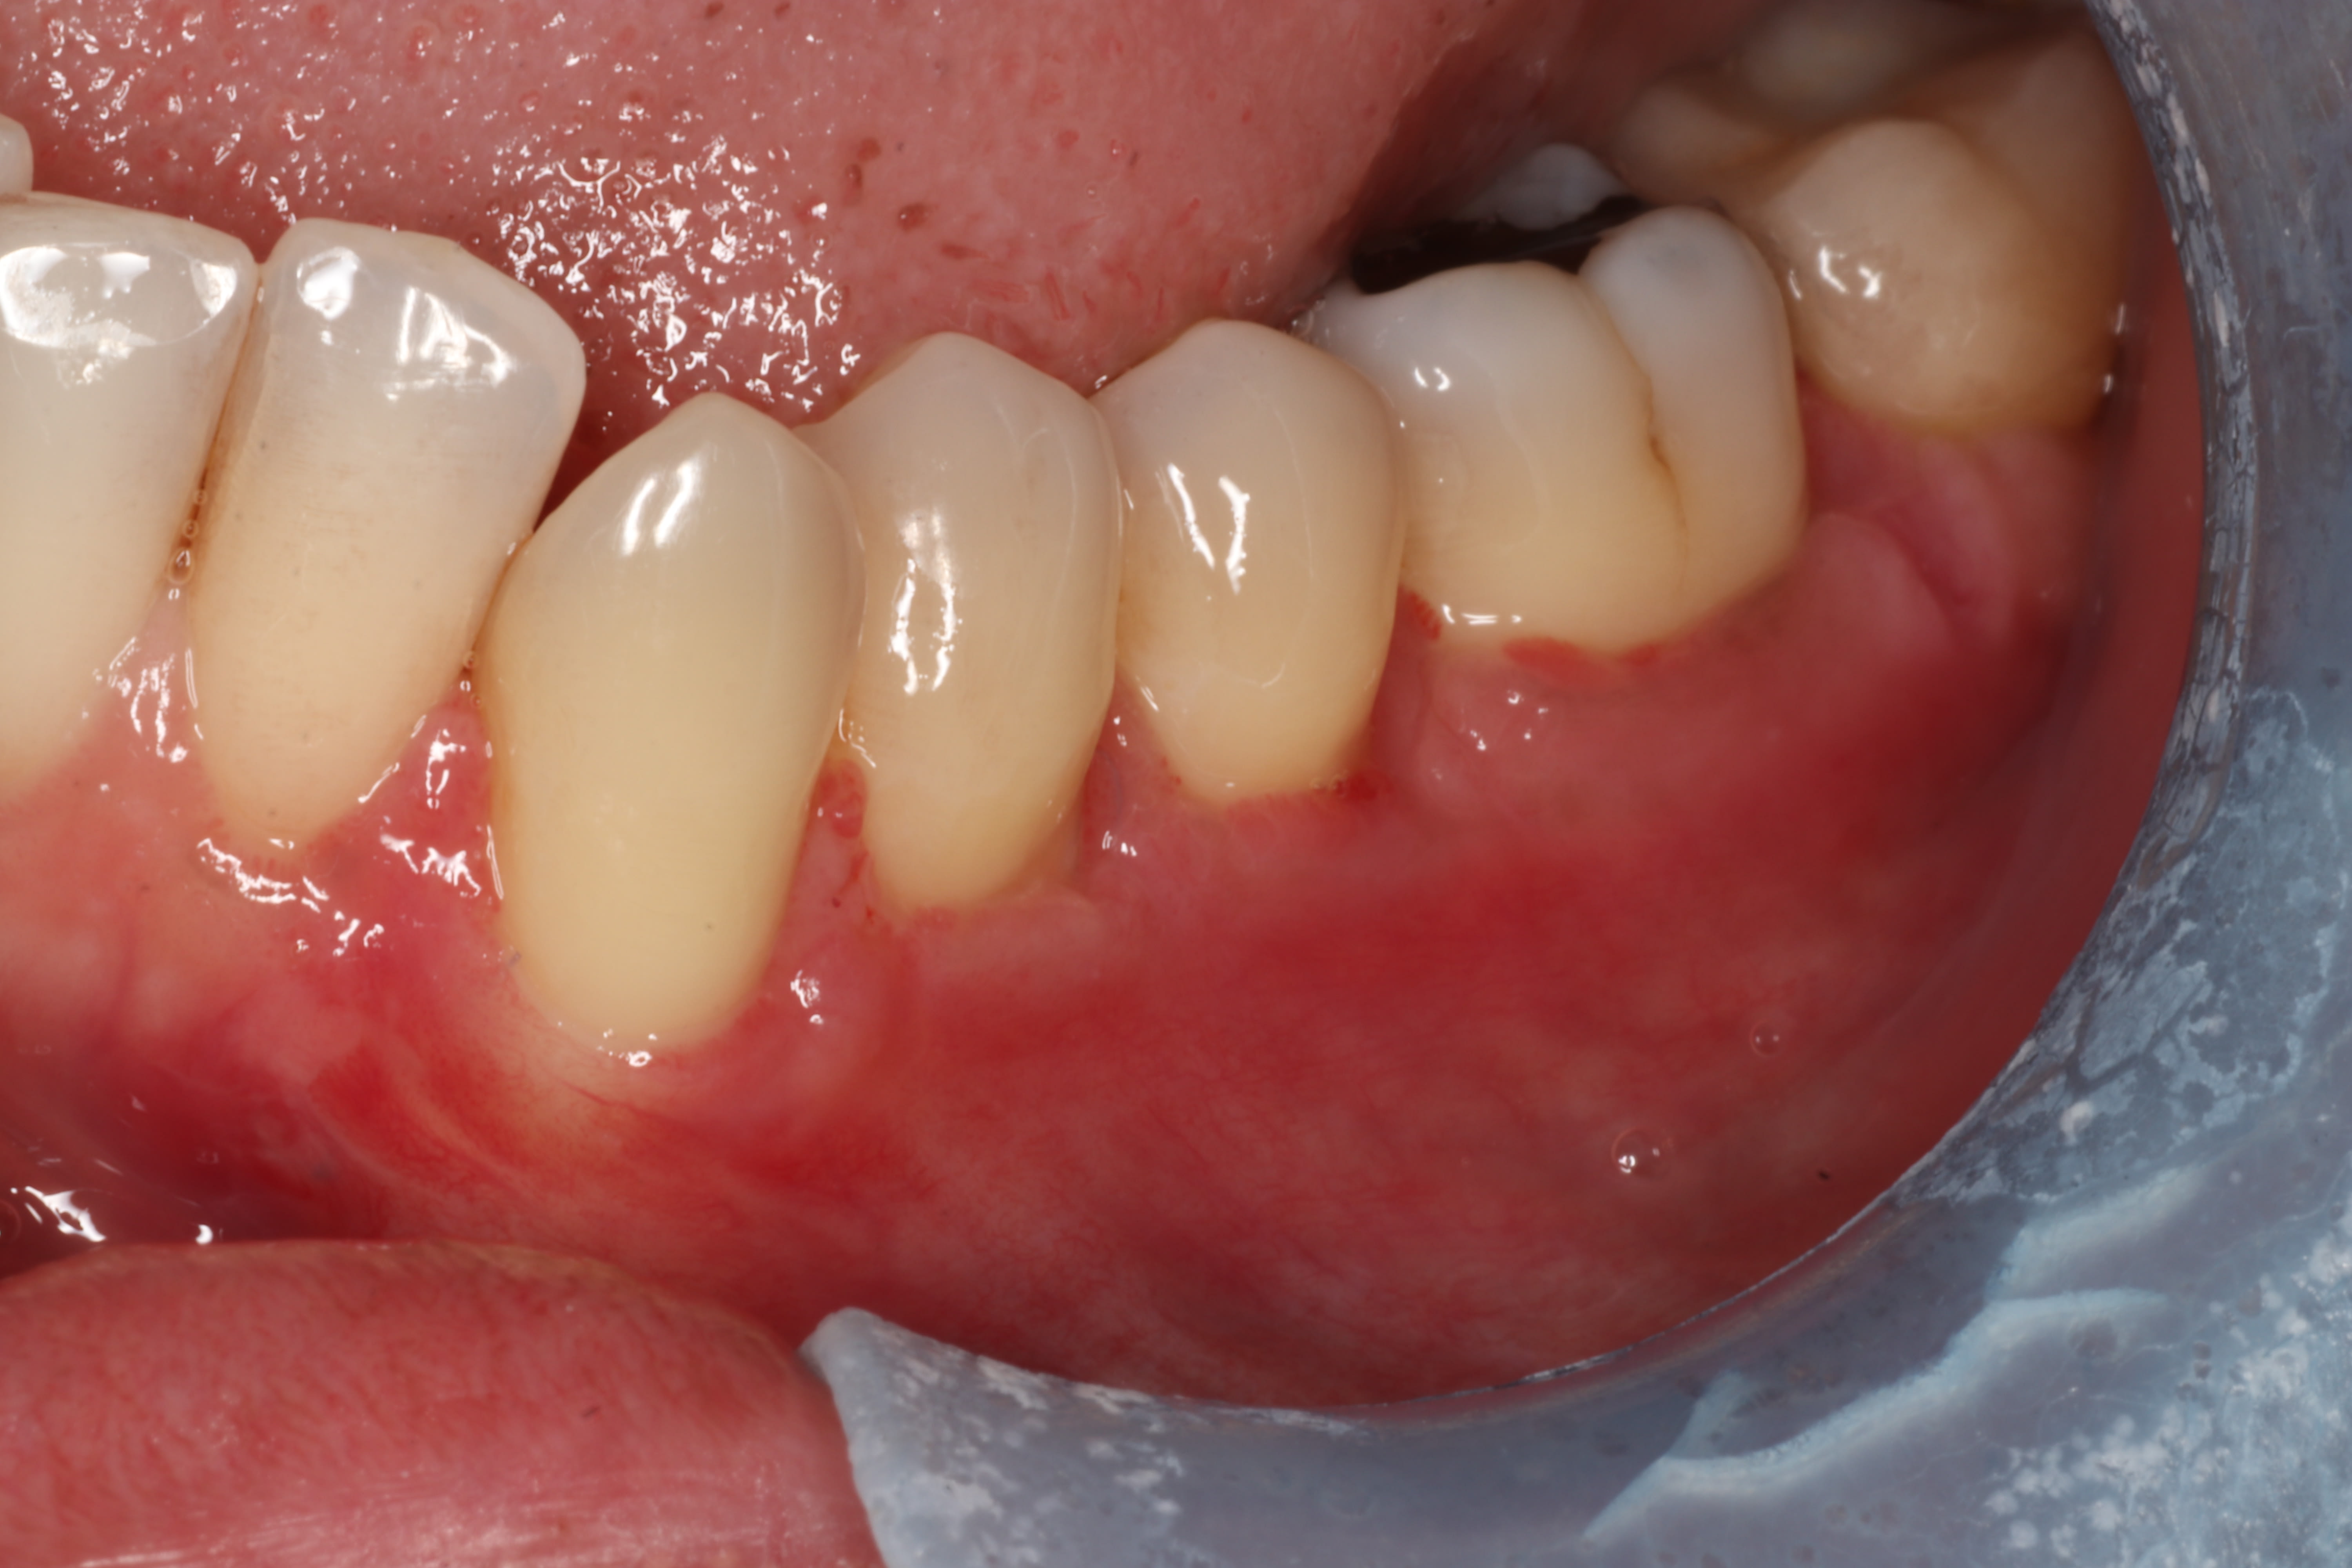

Contrôle à 14 jours, Zuchelli Style

Zone nettoyée curettes, piezo, fraises diamantés, EDTA.

Lambeau Zuchelli, avec décharge verticale en mésial.

Greffon palatin, dé-épithélialisé avec lame 15, sashimi style.

Sutures PGA 7-0 pour le greffon

Sutures Prolene 6-0 pour le lambeau

J'imagine qu'avec les fraises diamantés tu as adouci le bombé vestibulaire?

> J'imagine qu'avec les fraises diamantés tu as adouci le bombé vestibulaire?

oui, adoucir la jonction racine/email